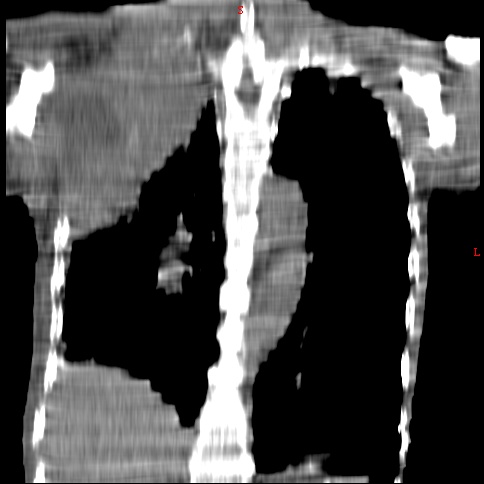

患者男,81岁,咳喘10余年,继往结核病史,发现胸部体表肿物(具体时间不详)就诊

右侧胸廓塌陷。右前上外侧胸壁软组织肿块,其内见有低密度影,肋骨呈溶骨性表现。右肺上叶见大量的间质纤维化表现。右侧膈肌上抬。

患者男,81岁,咳喘10余年,继往结核病史,发现胸部体表肿物

患者男,81岁,咳喘10余年,继往结核病史,发现胸部体表肿物。

考虑:1 右侧胸壁恶性肿瘤(多考虑:胸膜间皮瘤)。

2 继发性结核,右结核性胸膜炎伴胸壁结核性感染。